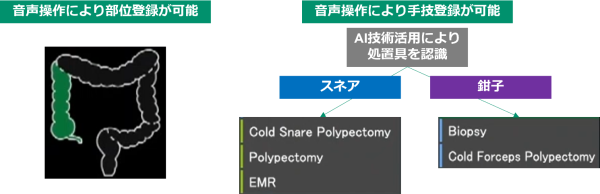

1.処置情報記録機能

AI技術の活用により、検査中の画面内で処置具を自動認識し、採取した検体番号と直前に撮影した静止画像を紐づけて保存する。さらに医師が部位情報、手技を発声するとそれらの情報も紐づけることができる。検査後レポート作成時に、医師は保存された処置情報を確認し、レポートへ反映すべき内容を確定する。レポート作成のために医師が処置情報を記憶するストレス、看護師がメモを取る手間の軽減に貢献する。

AI技術の活用による処置具の自動認識と、医師の音声操作による部位・手技の登録により、1回の処置に紐づけて病変画像、部位、手技、検体番号を検査中に記録することができる。医師による確認の後、これらの記録がレポートへ反映される。

「部位名」、「手技名」をそれぞれ音声入力することで、検査中に処置の情報を記録することができる。